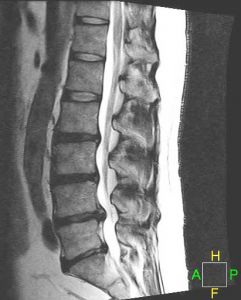

LUMBAR DISC HERNIATIONS ON MRI

A herniated disc may be diagnosed after a complete history and comprehensive physical exam. In addition, several diagnostic tests can be used. Imaging studies at the Virginia Spine Institute are usually a first step in understanding spine pathology. These include standing and bending X-rays to evaluate spinal alignment, stability and disc space height. Your doctor will determine whether additional tests are needed. An MRI is the standard imaging to assess disc and nerve pathology. An EMG may be used to determine which specific nerves are involved and the extent of possible nerve damage.